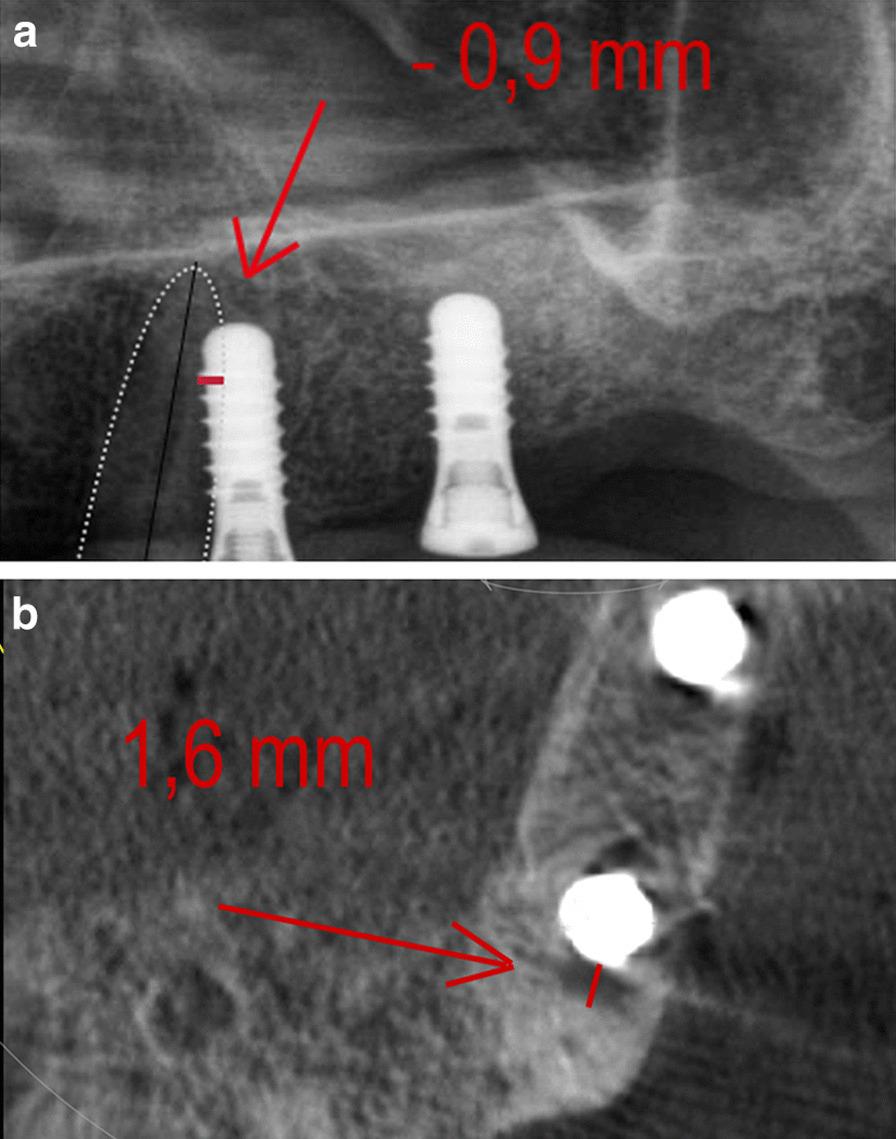

This study aimed to compare panoramic radiography (PAN) and cone beam computed tomography (CBCT) determinations of implant-to-root dimensions (IRD) in anterior and posterior maxillary regions, and to help determine in which instances increased radiation exposure from CBCT scans may be justified.

IRD measured by PAN (PAN-D) from implant-to-root sites (central incisor, lateral incisor, canine, first premolar, and second premolar) was collected from 418 implant sites in 110 adults. The CBCT technique was used as the reference method for the estimation of IRD. The PAN analysis equations were developed using stepwise multiple regression analysis and the Bland-Altman approach was applied to assess the agreement between PAN and CBCT methods.

The odds ratio that an implant at the canine-to-first premolar (9.7:1) (P = 0.000) or at the first premolar-to-second premolar region (4.5:1) (P = 0.000) belongs to the underestimation group was strong and highly significant. The root mean square error (RMSE) and pure error (PE) were highest for the canine-to-first premolar (RMSE = 0.886 mm, PE = 0.45 mm) and the first premolar-to-second premolar region (4.5:1) (RMSE = 0.944 mm, PE = 0.38 mm).

This study provides evidence of site-specific underestimations of available horizontal bone dimensions for implants when assessed by PAN. These data suggest that the canines and first and second premolars may have to be excluded when assessing root angulations via PAN.

本研究旨在比较全景放射摄影(PAN)和锥形束计算机断层扫描(CBCT)在前后上颌区域对种植体-根尺寸(IRD)的测定,并帮助确定在何种情况下 CBCT 扫描的辐射暴露增加可能是合理的。

从 110 名成年人的 418 个种植体部位收集了通过 PAN(PAN-D)测量的种植体-根部位(中切牙、侧切牙、尖牙、第一前磨牙和第二前磨牙)的 IRD。CBCT 技术被用作估计 IRD 的参考方法。使用逐步多元回归分析开发了 PAN 分析方程,并应用 Bland-Altman 方法评估 PAN 和 CBCT 方法之间的一致性。

犬牙到第一前磨牙(9.7:1)(P=0.000)或第一前磨牙到第二前磨牙(4.5:1)(P=0.000)的种植体属于低估组的优势比是强且高度显著的。犬牙到第一前磨牙(RMSE=0.886 毫米,PE=0.45 毫米)和第一前磨牙到第二前磨牙区域(4.5:1)(RMSE=0.944 毫米,PE=0.38 毫米)的根均方根误差(RMSE)和纯误差(PE)最高。

本研究提供了证据表明,当通过 PAN 评估时,可用水平骨尺寸对种植体存在特定部位的低估。这些数据表明,在通过 PAN 评估根角度时,可能需要排除犬牙和第一、第二前磨牙。